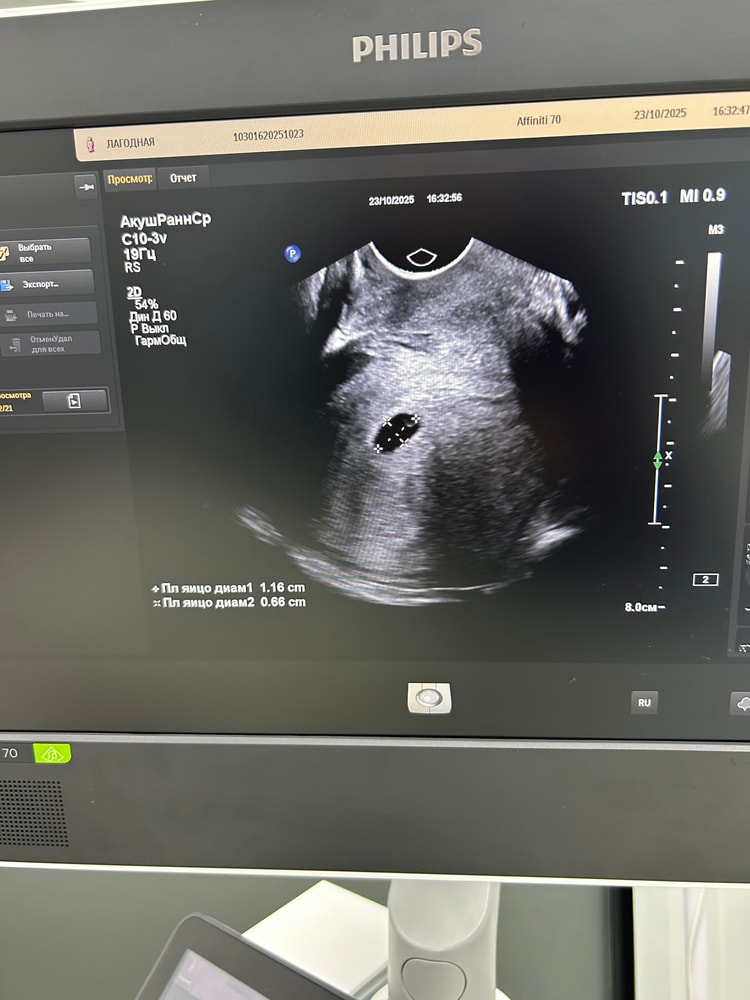

И вот переделала

Жалко нельзя видео скинуть 😂 та сердечко видно 🩷